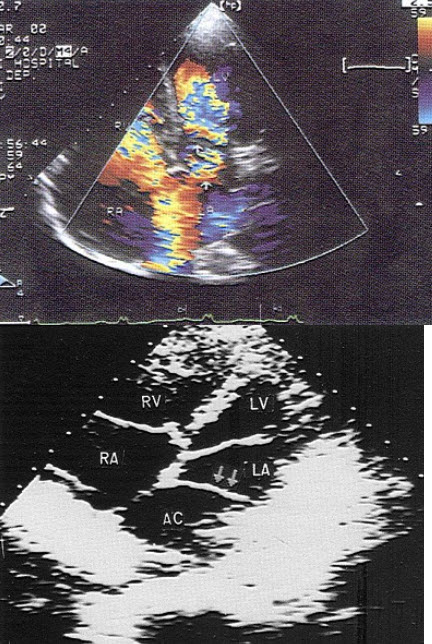

某患者收缩期超声心动图所示,提示()

A.二尖瓣狭窄

B.二尖瓣关闭不全

C.房间隔缺损

D.动脉导管未闭

E.以上都不是

30、单项选择题

该病例最有可能诊断()

A.肺静脉畸形引流

B.上腔静脉型房缺

C.Ⅱ孔型房缺

D.卵圆孔重开

E.下腔静型房缺